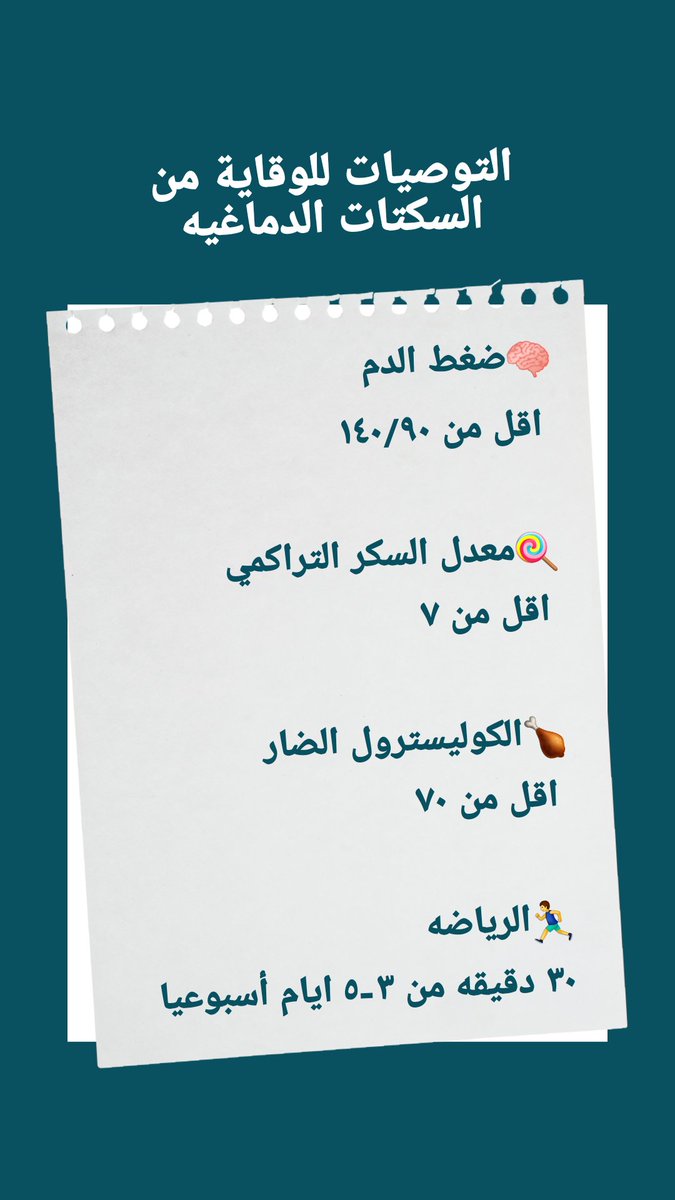

💥عوامل الخطورة

🧠ارتفاع الضغط

🧠السكري

🧠الكوليسترول

🧠التدخين

🧠قلة النشاط البدني

#السكته_الدماغيه_الاقفاريه

🧠العلاج الوقائي

خطوة هامه لمنع إعادة الاصابه مستقبلا

(معرفة السبب الأساسي والسيطرة عليه)

♦️متابعة

(سكر/ضغط/كوليسترول/تدخين/رياضه)